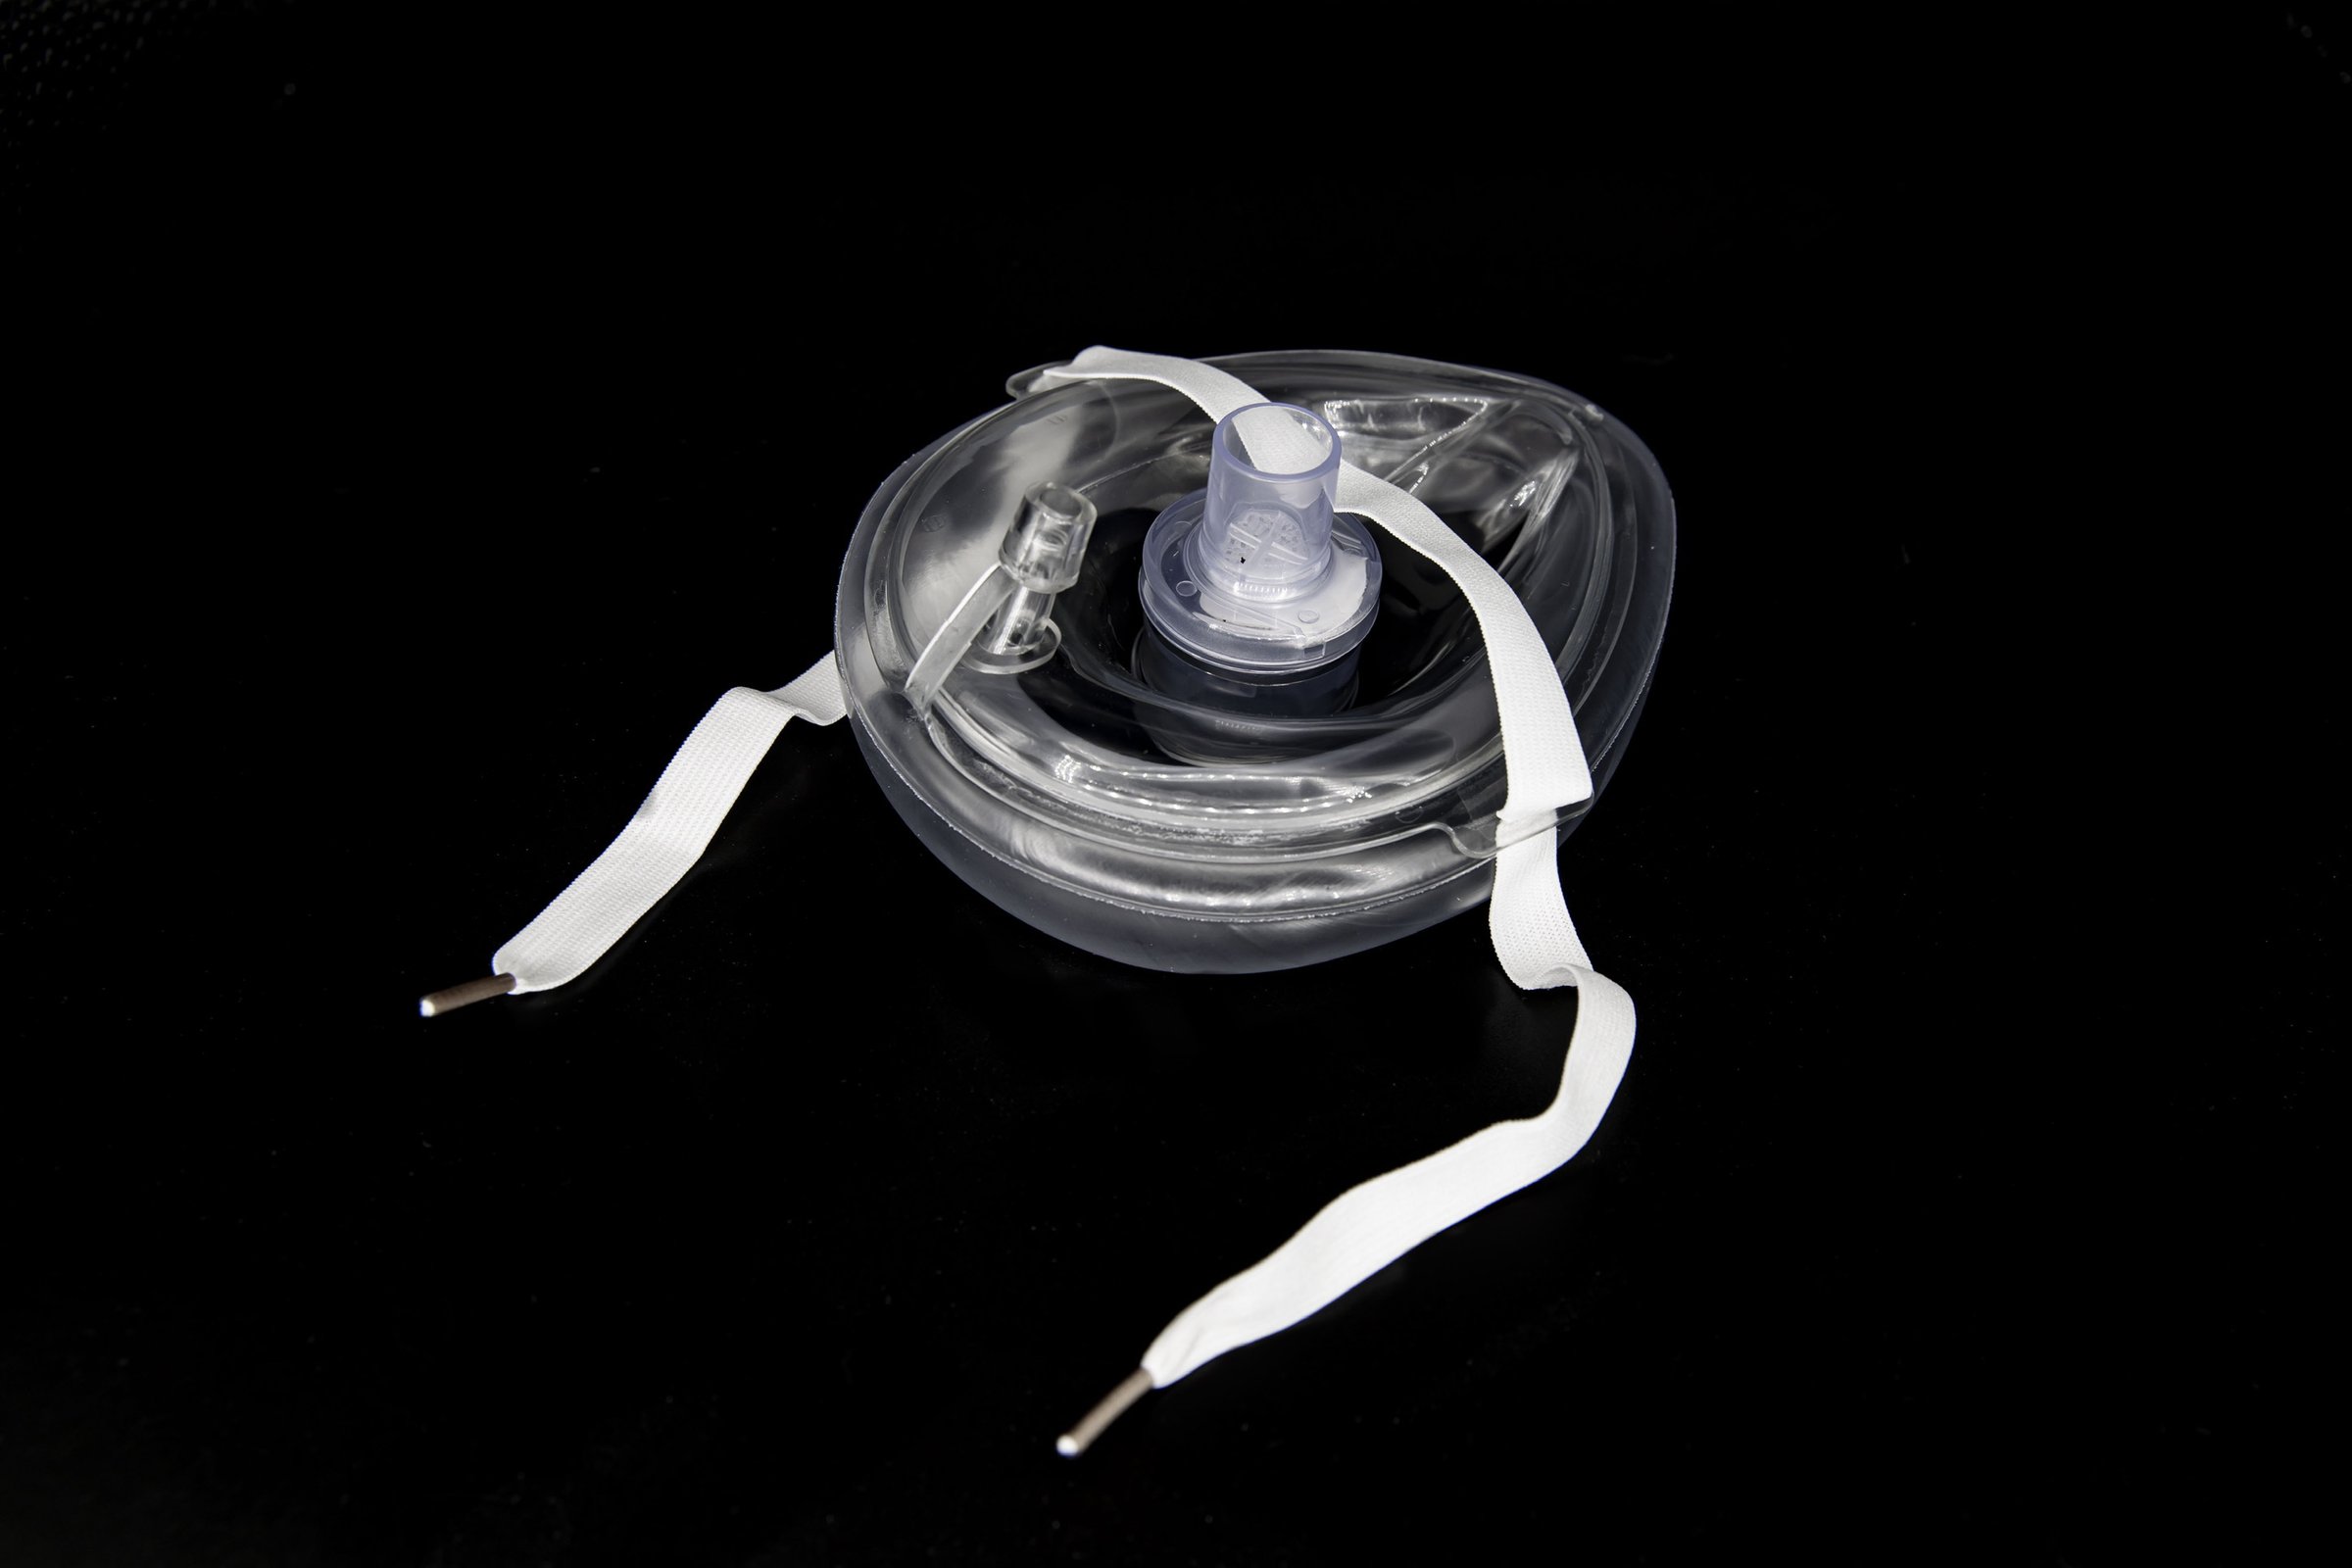

Masque de poche adulte (avec O2 et valve) – unitaire

Masque de poche adulte incluant:

- Extension « anti-retour »

- Entrée oxygène

- Filtre haute efficacité (99.2%)

- Attache

- Dans sac de plastique avec fermoir

Sans boîtier

Format : Unitaire